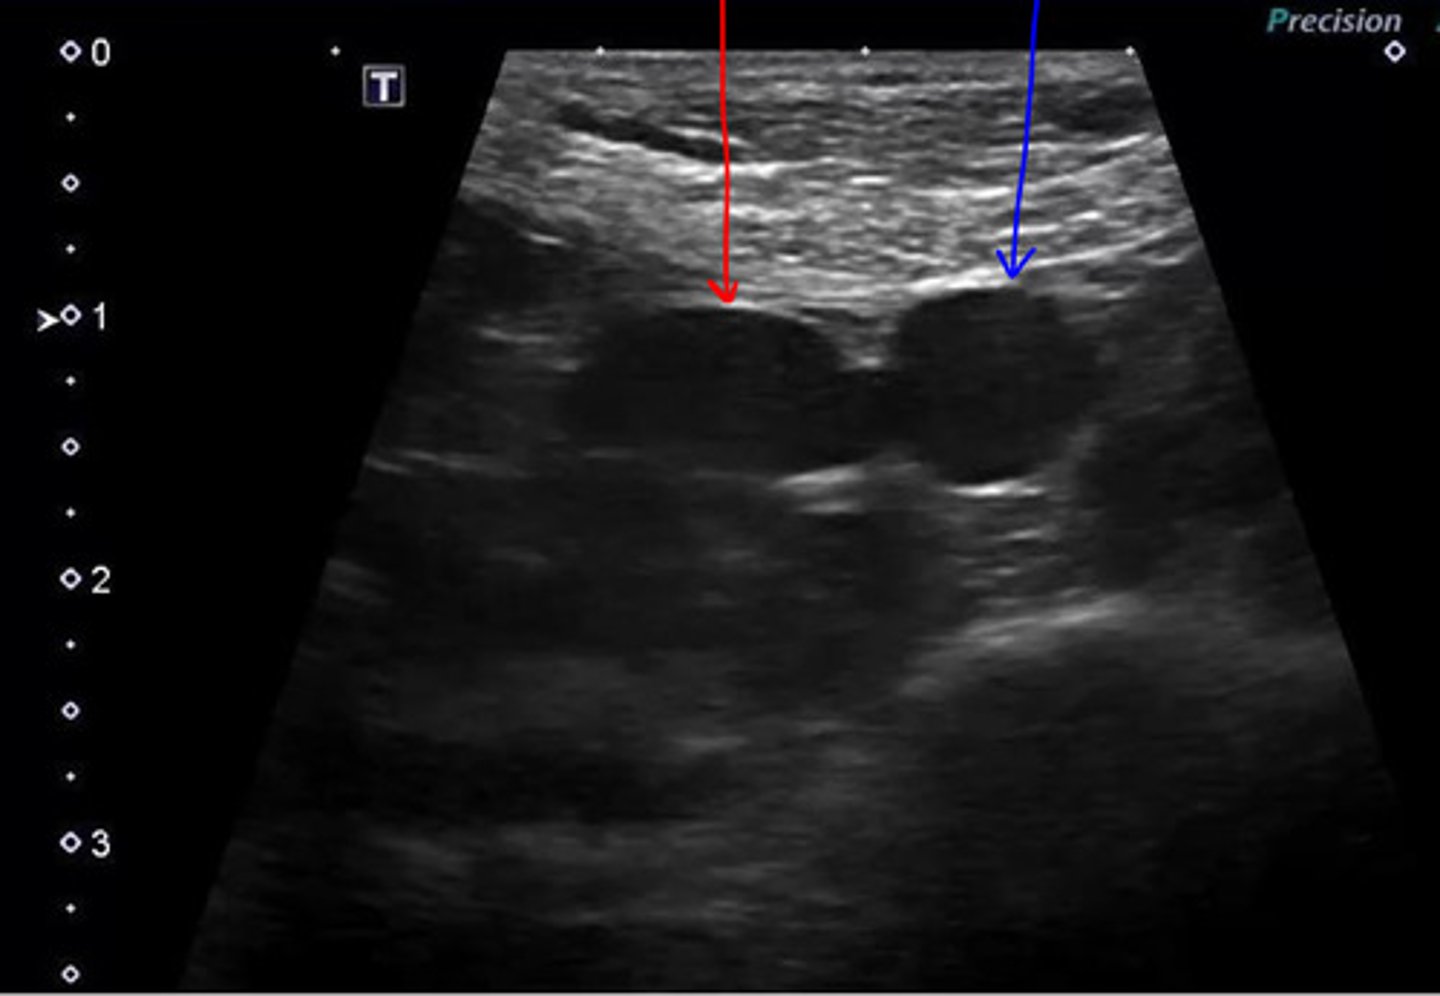

medial iliac lns.

ID lymph node

medial iliac lns.

ID lymph node (hint: trifurcation near)

laterally adjacent to the external iliac arteries

location of the medial iliac lns?

most cranial in the pelvis (and LARGEST)

the medial iliac lns. are the most cranial or caudal in the pelvis?

lower urogenital tract, pelvis, and pelvic limbs

the medial iliac lns. drain what three areas?

-hypoechoic relative to surrounding fat

-hyperechoic relative to vessels

echogenicity of medial iliac lns.?

thin hyperechoic

what is the capsule of the medial iliac lns. echogenicity?

elongated oval shape

what is the shape of the medial iliac lns.?